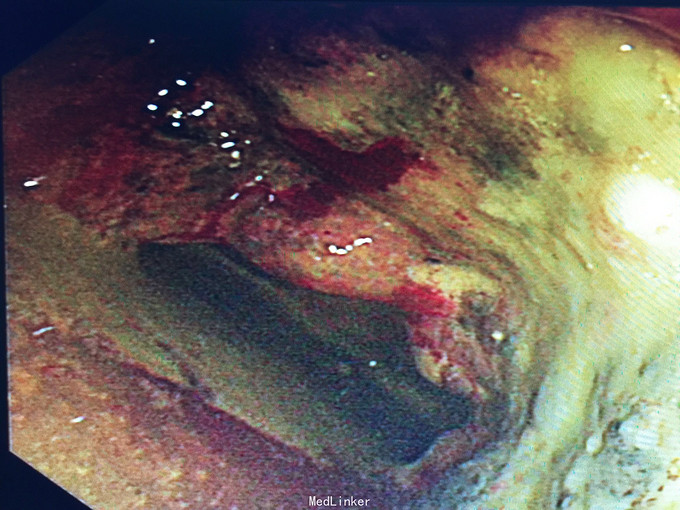

诊断:直肠癌, 预约结肠镜检查:距肛缘4cm见环肠肿物,凸凹不平,表面覆污秽苔,质硬,界不清。 病理结果为直肠腺癌。 病人回当地医院接受治疗。